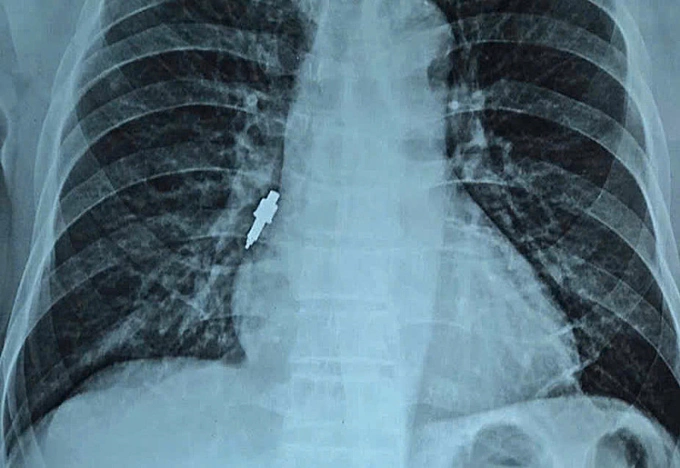

Dị vật kim loại nằm sâu trong đường thở. Ảnh: Bệnh viện cung cấp

Ngày 26/11,đại diện viện cho biết nội soi gắp thành công dị vật nằm sâu trong phế quản phải của bệnh nhân. Dị vật là một dụng cụ nha khoa bằng inox,trơn nhẵn,dài 2,5 cm và có đường kính lớn nhất lên tới 1 cm.

Trước đó,bệnh nhân đến viện khám do ho kéo dài,cơn ho ngày càng tăng nặng. Ông cho biết hai tuần trước đã làm thủ thuật đặt trụ răng giả (implant) tại một phòng khám tư nhân. Trong quá trình thực hiện,nha sĩ thông báo làm rơi một dụng cụ nhưng không xác định được vị trí. Khi về nhà,ông bắt đầu ho nhẹ rồi chuyển biến xấu dần.